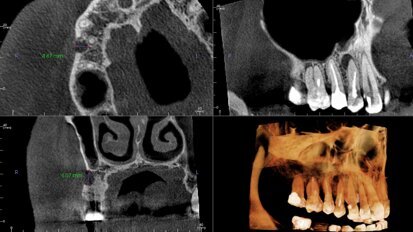

Cyfryzacja gabinetu to lepsze przewidywanie wyników leczenia i skuteczności terapii stomatologicznych

O nowoczesnych narzędziach wykorzystywanych w codziennej praktyce ortodontycznej, konieczności współpracy lekarzy i zapewnienia pacjentom ...